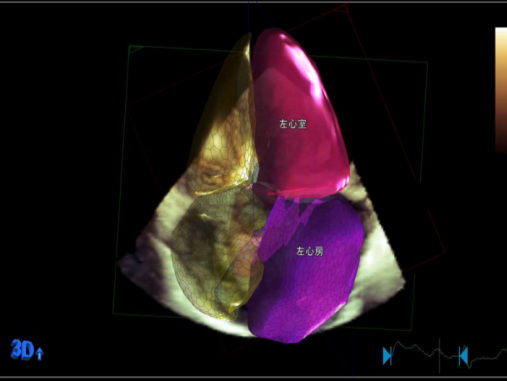

入院检查:甲状腺功能、凝血功能、血常规、hs-CRP均正常范围,eGFR 71ml/min/1.73㎡,BNP 3881.7pg/ml ,肝功能“TBIL 41.2umol/L DBIL 17.1 umol/L IBIL 24.1umol/L”;心电图提示“异位心律,心房颤动,偶发室早,QRS 波宽度113ms”;心超提示“扩张型心肌病 ,全心扩大(左房内径 64mm,左心室舒张末期内径82.1mm),左室壁运动弥漫性减低,二尖瓣中度反流,三尖瓣轻度反流,主动脉瓣轻-中度反流,心律失常,左室收缩功能减低(LVEF 37%)”;心肌MR提示“扩张型心肌病,全心扩大,LVEF 22.4%,左心室基底段-中央段间隔壁心肌中层见点、线样延迟强化”;动态心电图“心房颤动24小时总心搏114767次,平均90次/分,最慢67次/分,最快164次/分,多源室早(1918次,包括单发室早1854次,成对28对,短阵室速2阵)”。

超声心动图

心肌磁共振